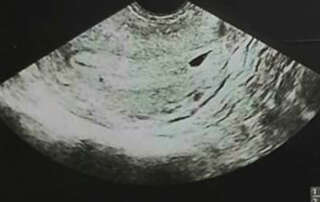

Hysteroscopic removal of Retained Intra-uterine Fetal Bone which causes secondary infertility: A case report

DOI: 10.36205/trocar1.2021003